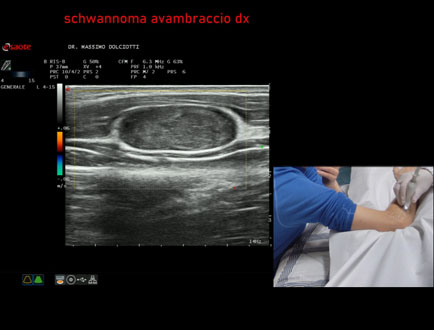

Età Paziente: M 48 anni

Motivazione dell'esame: da circa 1 anno rilievo di tumefazione all'avambraccio destro.

Commento all'esame: le immagini ed il video documentano, all'avambraccio destro, all'interno del muscolo estensore delle dita, formazione ipoecogena a margini definiti, delle dimensioni di 28,5 mm per uno spessore di 12,1 mm, con modesti segni di vascolarizzazione intra nodulare, da ricondurre, come prima ipotesi, a Schwannoma.

Conclusioni: schwannoma all'avambraccio destro (schwannoma of the right forearm).

In collaborazione: Dr.ssa Marica Manfredi - Ancona, Dr. Ilir Qose - Ancona

Presentazione: Dr. Massimo Dolciotti - Ancona

Elaborazione digitale: Andrea Dini - Ancona

VISUALIZZA IL VIDEO